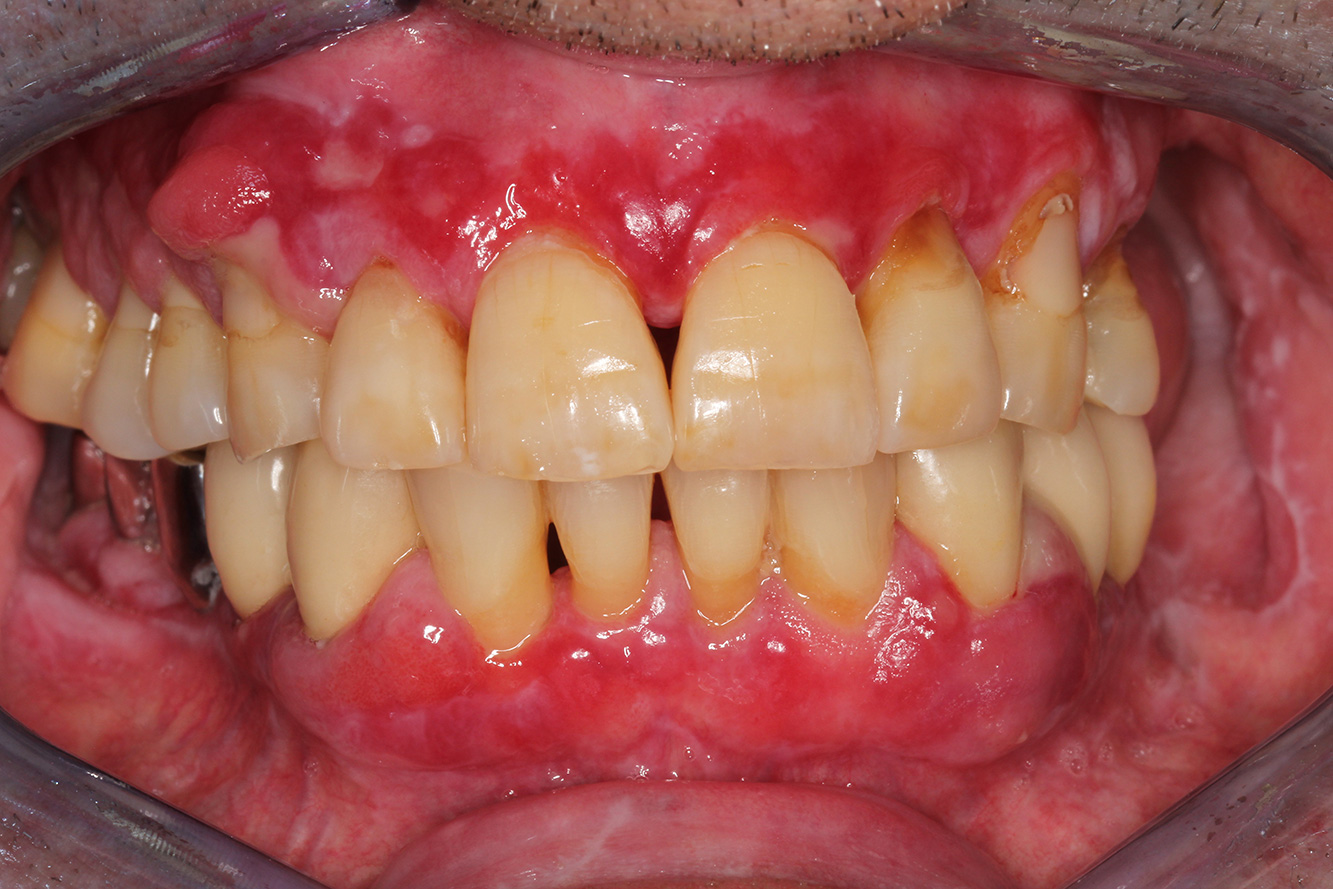

Der gesunde Patient mit parodontaler Vorerkrankung & Periimplantitis

Ein 52-jähriger Patient stellt sich zur Präventionssitzung vor. Der Patient hat keine Allgemeinerkrankungen und nimmt keine Medikamente ein. Er hat verschiedene zahnärztliche Versorgungen und zudem zwei aktive kariöse Läsionen. Außerdem verfügt der Patient über vier Implantate (2., 3. und 4. Quadrant). Es zeigt sich eine parodontale Vorerkrankung (Stadium IV, Grad B). Derzeit herrschen stabile parodontale Verhältnisse, lediglich am Implantat regio 36 zeigen sich Sondierungstiefen (ST) von 5 mm. Zudem lässt sich eine Gingivitis feststellen. mehr Infos